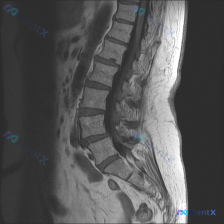

整理到一份腰椎影像资料,有点意思,也有点容易踩坑。 先放核心影像表现(腰椎矢状位T2WI): 1. L2/L3、L3/L4椎间盘信号尚可,L4/L5、L5/S1 T2信号明显降低(黑盘征); 2. L4/L5、L5/S1椎间盘后缘突出,明显压迫硬膜囊,相应节段脑脊液间隙变窄/消失; 3. 腰椎生理前...

整理了一份影像分析资料,先给大家看核心信息: - 给出的是 腰椎MRI T2序列矢状位 - 用户提示的观察重点是:脊柱侧弯 - 影像明确报了这些: - L4/L5、L5/S1椎间盘退变(黑盘征、高度变窄) - 这两个节段椎间盘向后突出,硬膜囊前缘受压 - 同节段椎管狭窄倾向 - 部分终板T2信号增高...

整理了一份腰椎MRI的影像分析资料,先抛出来大家讨论下阅片思路。 基础影像发现(先列客观的): - 腰椎多节段椎间盘T2信号减低(黑盘征),L2-L3到L5-S1都有 - L4-L5椎间隙变窄,椎间盘明显后突,硬膜囊受压很明显,椎管也窄了 - L5-S1也有椎间盘后突压迫硬膜囊 - 腰椎生理前凸变直...

整理到一份影像资料,有点意思: 只有腰椎MRI T1加权矢状位,能看到: 1. 腰椎生理前凸存在,但L5/S1有明显的腰椎滑脱(L5相对于S1向前移位) 2. 下腰椎多个椎间盘信号减低、L4/L5和L5/S1椎间隙变窄 3. 对应节段终板有Modic II型改变(脂肪化) 4. L4/L5及L5/S...

整理了一份病例资料,有点意思: - 主诉提的是 Scoliosis(脊柱侧弯) - 但只给了 腰椎MRI-T2加权像(矢状位) - 影像上能看到: - L4/L5、L5/S1 节段椎间盘T2信号明显减低,髓核脱水退变 - 相应节段椎间隙高度有丢失 - 椎间盘向后突出,尤其是L4/L5、L5/S1水平...